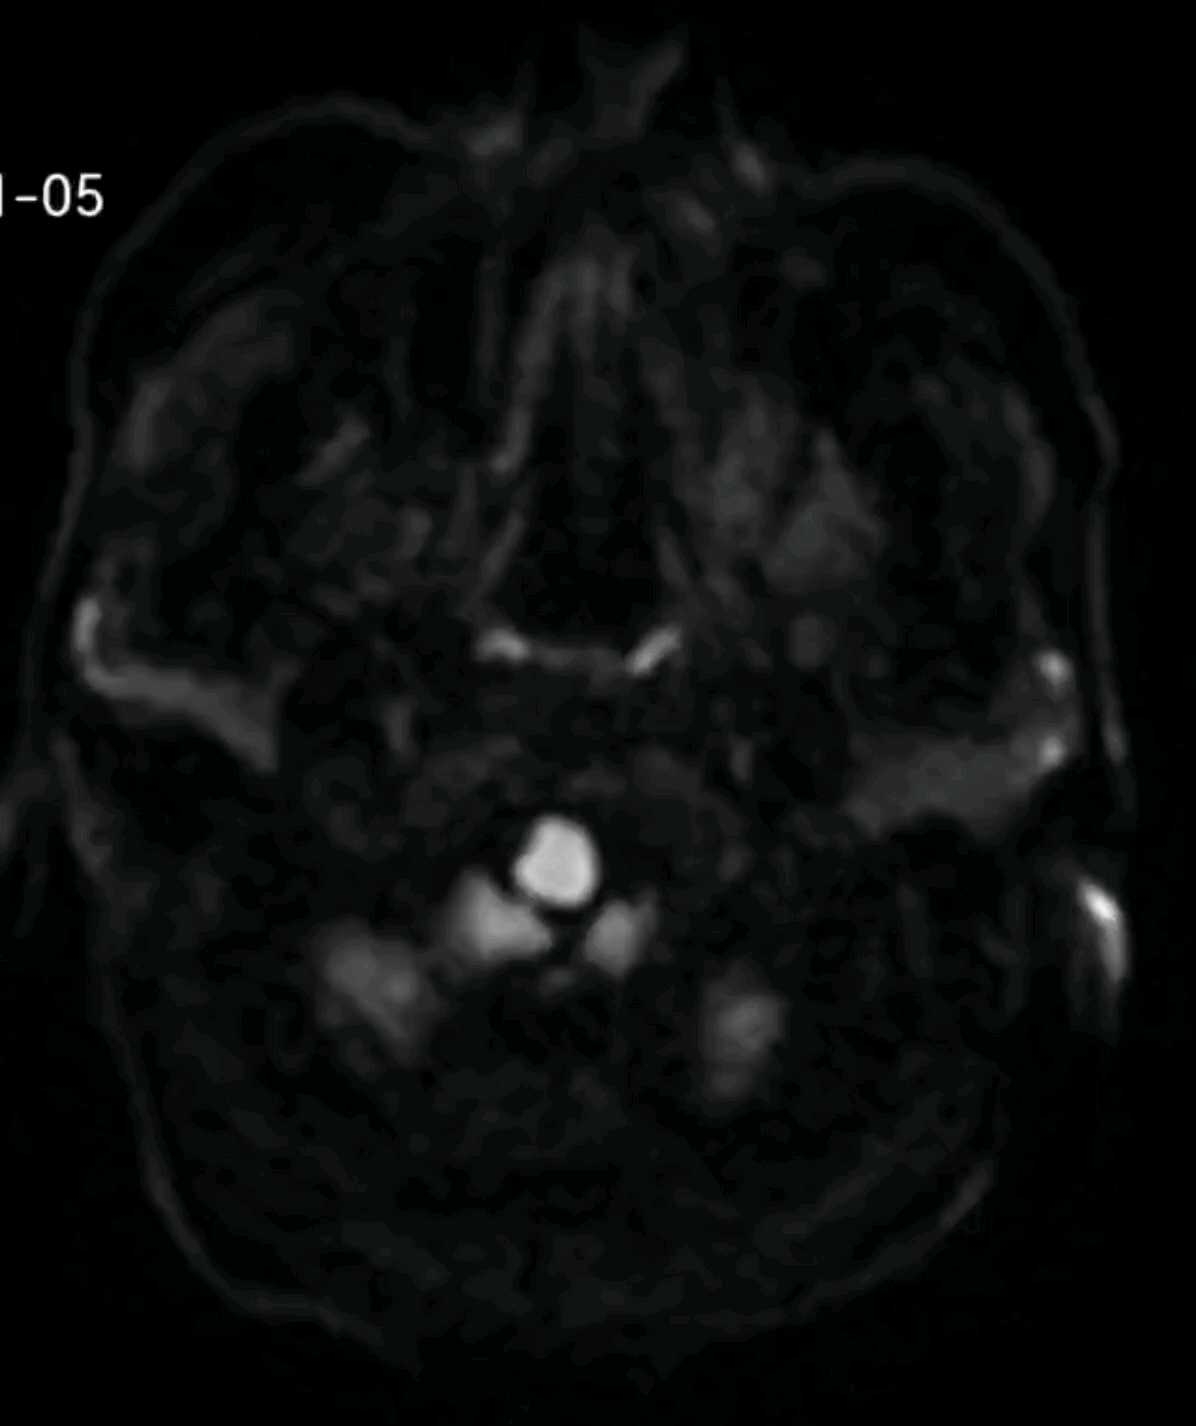

老年男性,急性起病,头痛,双耳听力下降伴胡言乱语10天余。